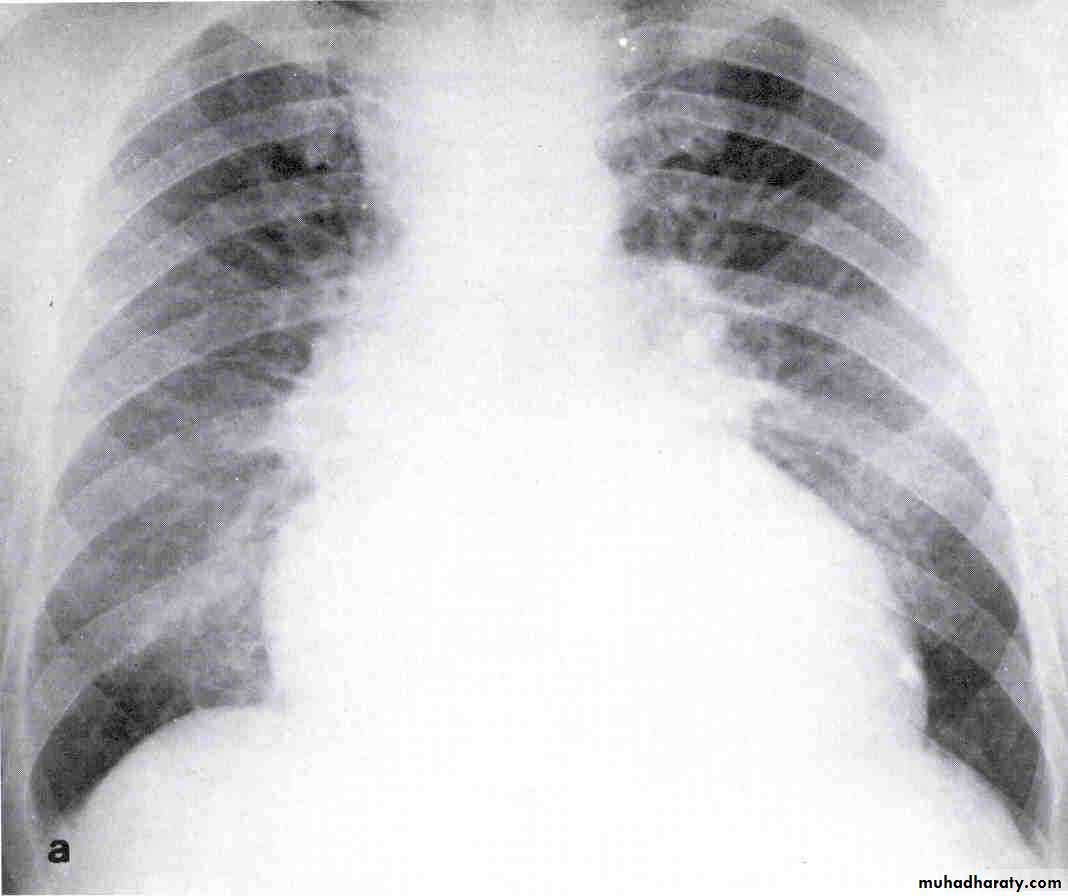

Chest X-ray

Look for Heart size

Pulmonary vascular markings

COPD, pneumonia, Pneumothorax, widened mediastinum

Pleural effusions

Chest X- ray

Systolic versus diastolic failure

SYSTOLIC DYSFUNCTION

DIASTOLIC DYSFUNCTION

Dilated cardiac chambers.

Cardiomegaly on CX-ray.

Low EF < 40 %.

Worse prognosis.

Normal size or LVH.

Pulmonry congestion +normal cardiac size.

Normal EF > 40 % ,E/A< 1

Good prognosis.